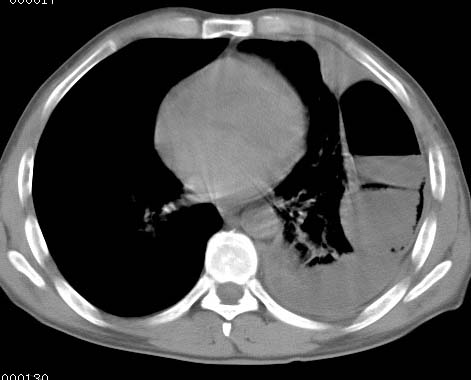

标题: CT10145:男性,30岁,活动后气促2月余.隔疝伴胸腔积液.右上肺结 [打印本页]

男性 病人 30岁,活动后气促2月余.隔疝伴胸腔积液.右上肺结核!

左侧胸腔积液,并胸腔内见多个含液 气组织,并相互重叠。影像特征很特殊,应该是“膈疝”。支持!

左侧膈疝,及左侧胸水,双上肺结核。

左侧胸腔包裹性液气胸未除。

左膈疝?